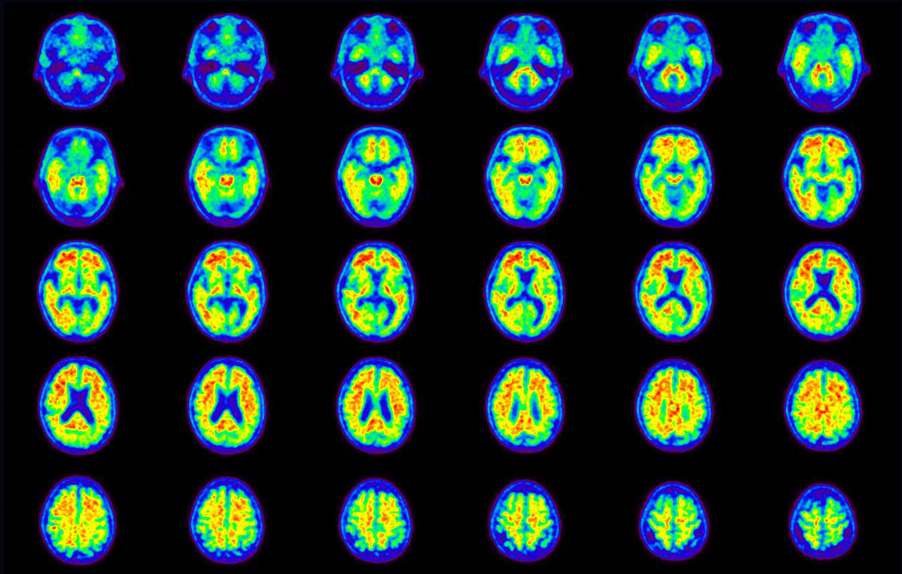

Head / Case5 : Amyloid

Axial

Courtesy : Kindai University Hospital

- Imaging protocol

- Injected dose: 4.27 MBq/kg, 18F-Flutemetamol

- Uptake time: 99 minutes

- Scan time: 20 minutes